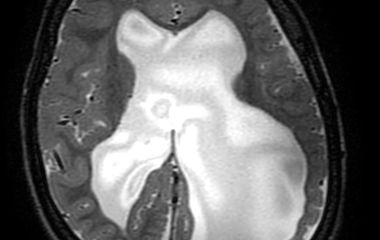

Ein Hydrocephalus entsteht durch eine Störung des Hirnwasserflusses oder der Aufnahme des Hirnwassers ins Körpersystem. Dies kann zu einer Vergrößerung der Hirnkammern und einem erhöhten Druck im Kopf führen. Typische Symptome sind ein schnell wachsender Kopfumfang, Kopfschmerzen oder Entwicklungsverzögerungen. Die Behandlung erfolgt meist operativ durch eine Ableitung des Hirnwassers, z. B. mit einem Shunt-System oder einer endoskopischen Technik.